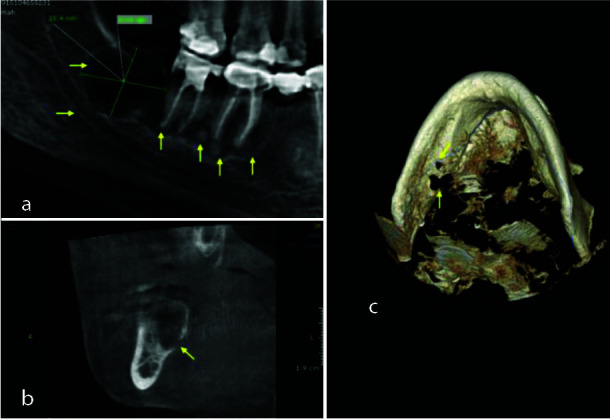

Cemento-osseous dysplasia (COD) is classified, by the World Health Organization as a benign fibro-osseous lesion related to the tooth and periapical area of the jaws and is considered as a benign reactive process appearing from the apical periodontium in close relation with the apices of teeth. Usually, it is asymptomatic, discovered accidentally, and affecting particularly middle-aged African women. There are four subtypes distinguished of the lesion: periapical (PCOD), focal (FCOD), florid (FLCOD) and familial florid cemento-osseous dysplasia (FFLCOD). Pseudocysts found in the jaws go by various names, including solitary bone cyst, traumatic bone cyst, or simple bone cyst (SBC). These two pathologies have been reported separately; however, their co-occurrence remains rare and the first case of FLCOD with co-occurrence of SBC was reported by Melrose et al. in 1976 and later a few cases been reported in the literature. The aim of this report is to describe a case of a 46-year-old oriental female diagnosed with FLCOD with co-occurrence of SBC. Under local analgesia, a surgical exploration of the cyst was performed. In addition, a biopsy with a trephine was done in the region of missing right first mandibular molar. Based on the patient clinical, radiographic, and histological findings, a diagnosis of FLCOD was made in co-occurrence with a mandibular SBC. An examination of another female family member unveils a distinctive case, and the familial factor has been ruled out. No further treatment was planned and only follow-up was suggested.

根据世界卫生组织的分类,牙骨质发育不良(COD)是一种与牙齿和颌骨根尖周围有关的良性纤维骨病变,被认为是一种良性反应性过程,出现在与牙齿根尖密切相关的根尖牙周。它通常无症状,偶然发现,主要影响中年非洲妇女。这种病变可分为四种亚型:根尖周型(PCOD)、局灶型(FCOD)、花斑型(FLCOD)和家族性花斑牙骨质发育不良型(FFLCOD)。颌骨中发现的假性囊肿有多种名称,包括单发性骨囊肿、创伤性骨囊肿或单纯性骨囊肿(SBC)。1976年,Melrose等人报告了第一例同时伴有SBC的FLCOD病例,后来又有一些病例在文献中出现。本报告旨在描述一例被诊断为 FLCOD 并发 SBC 的 46 岁东方女性病例。在局部镇痛的情况下,对囊肿进行了手术探查。此外,还在右下颌第一臼齿缺失区域进行了穿刺活检。根据患者的临床、影像学和组织学检查结果,诊断为下颌SBC同时伴有FLCOD。对另一名女性家庭成员的检查发现了一个独特的病例,并排除了家族因素。没有进一步的治疗计划,只建议进行随访。